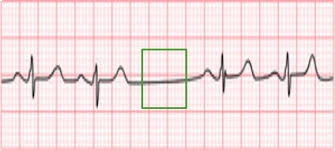

¡En Tabasco, el Dr. Carlos Aguila Bravo destaca como un cardiólogo intervencionista que utiliza métodos actualizados en cardiología! No todos los especialistas en la región se mantienen al día con las últimas técnicas practicadas en países de primer mundo, pero el Dr. Aguila Bravo es diferente. Con su compromiso en brindar la mejor atención cardiológica, te ofrece una experiencia médica vanguardista y actualizada. No te conformes con menos cuando se trata de tu salud cardiovascular. Agenda tu consulta con el Dr. Carlos Aguila Bravo en Tabasco y descubre cómo su enfoque innovador puede marcar la diferencia en tu bienestar. ¡Tu corazón merece lo mejor y él se asegurará de brindártelo!